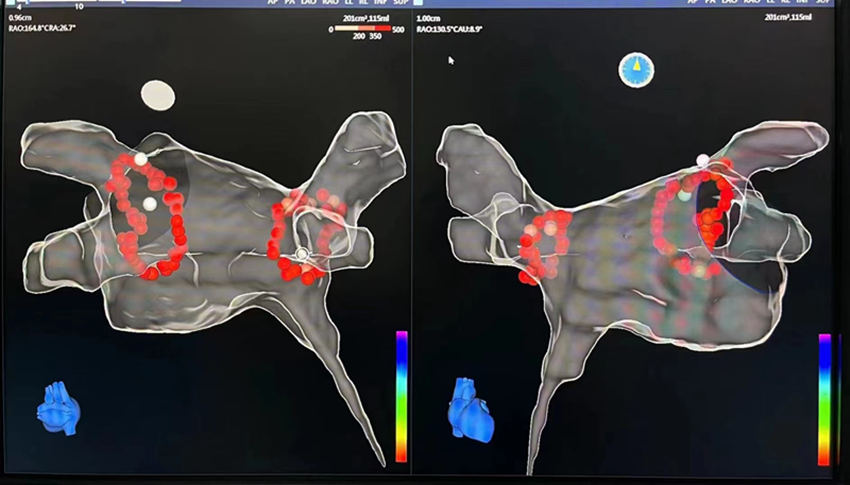

近日,兰大二院心血管内科二病区吴强主任团队在省内率先使用国产三维标测技术,成功为一例心房颤动患者实施射频消融术。该手术填补了省内国产设备在复杂心律失常射频消融术应用中的空白,为患者提供了更多新的选择。

患者女性,54岁,4年前曾在外院因“阵发性室上性心动过速”行射频消融术,术后偶有心悸症状。此次因“阵发性心房颤动”入院,完善检查后,在国产三维标测系统引导下,为患者实施了慢径改良及环肺静脉电隔离术,术后患者恢复良好,现已康复出院。

心脏射频消融术是根治心动过速最有效的方法,也是心房颤动的一线治疗策略。随着三维定位实时标测技术的引进,房颤等复杂心律失常的介入手术治疗取得了突破性进展。但由于设备及器材均依赖进口,价格高昂,技术应用推广慢,部分患者治疗受限。此次国产化后将有助于该技术的快速应用,造福广大患者。